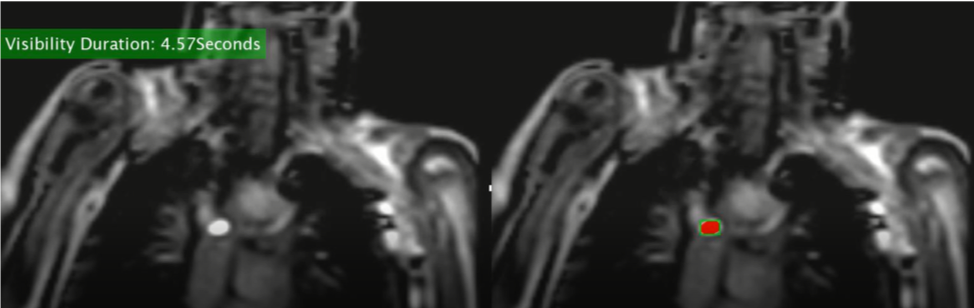

The second challenge involved visualizing the balloon in the heart during the MRI procedure. An MRI takes an image of a single plane at any given time. If the balloon is not in that plane, the cardiologist cannot see it, so any movement of the balloon is done blindly. This results in the patient having to potentially be repositioned, lengthening the anesthesia time. Dr. Arar asked us to find a way to track the amount of time the balloon is seen during a procedure. By knowing this information, the cardiologists can evaluate the procedure after it is finished to discuss what could have been done differently to keep the balloon in view longer. By determining what adjustments can be made, future procedures can be more efficient, shorter, and safer. Our team used a process called “thresholding” to segment the balloon on the MRI image and count the number of frames it appeared in. This allowed us to calculate the percentage of time the balloon was seen.